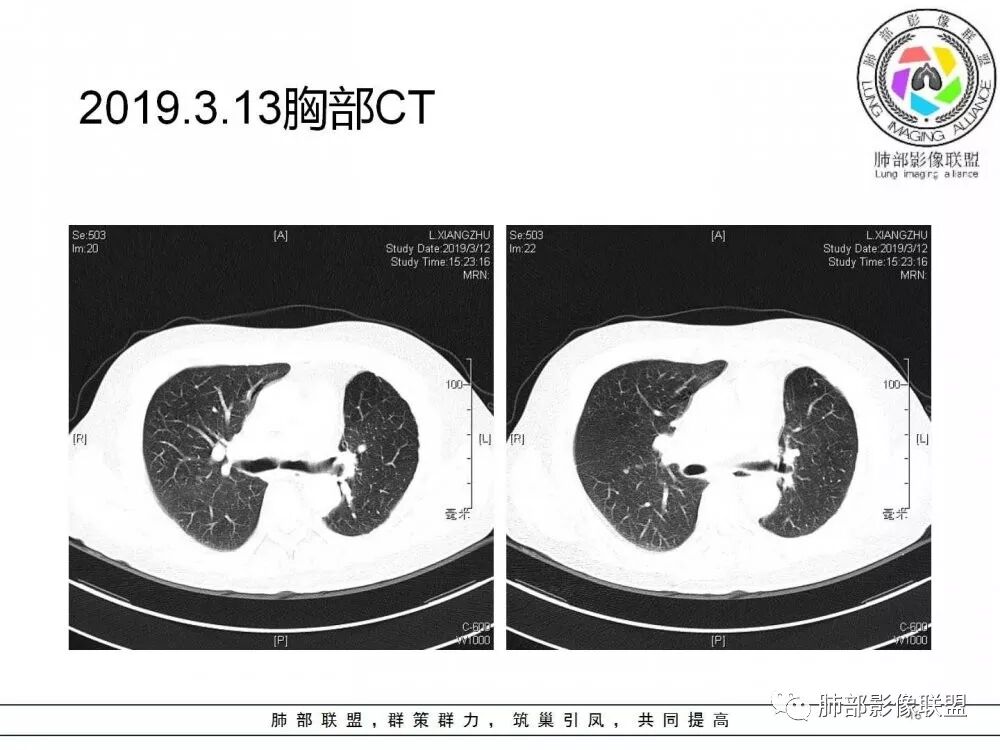

右肺上叶后段实性结节,部分边缘磨玻璃,周围可见多发小结节,病灶逐渐进展,临床有肺癌病史、LGG4相关病变、激素长期使用史,考虑1隐球菌。2肺癌复发。3LGG4相关性肺改变,病变局限,应该不符合。

右肺上叶后段多发实性结节,边缘收缩,葫芦兄弟,临床有激素治疗史,考虑隐球菌。

肺癌病史,长期激素实用史,IgG4相关病史,治疗有抗癌和激素治疗,肺部多发胸膜下小结节,边缘模糊,有些结节有进展,葫芦兄弟,考虑隐球菌。

右肺上叶后段实性结节,周围可见多发小结节,病灶逐渐进展,临床有肺癌病史、LGG4相关病变、激素长期使用史,考虑1隐球菌。2肺癌复发。3LGG4相关性肺改变

病灶从2月份就开始有,应该最早说是1月7号就有了,到3月13号稍微增大一点,到后面几乎没变化,到5月份好像稍微大一些,炎性应该是炎性,犹豫的是这个炎性到底什么病变呢?其实本没变化,它特点一个是在叶裂上,跟血管关系密切,但是病灶边缘稍收缩,病灶没有太大变化。